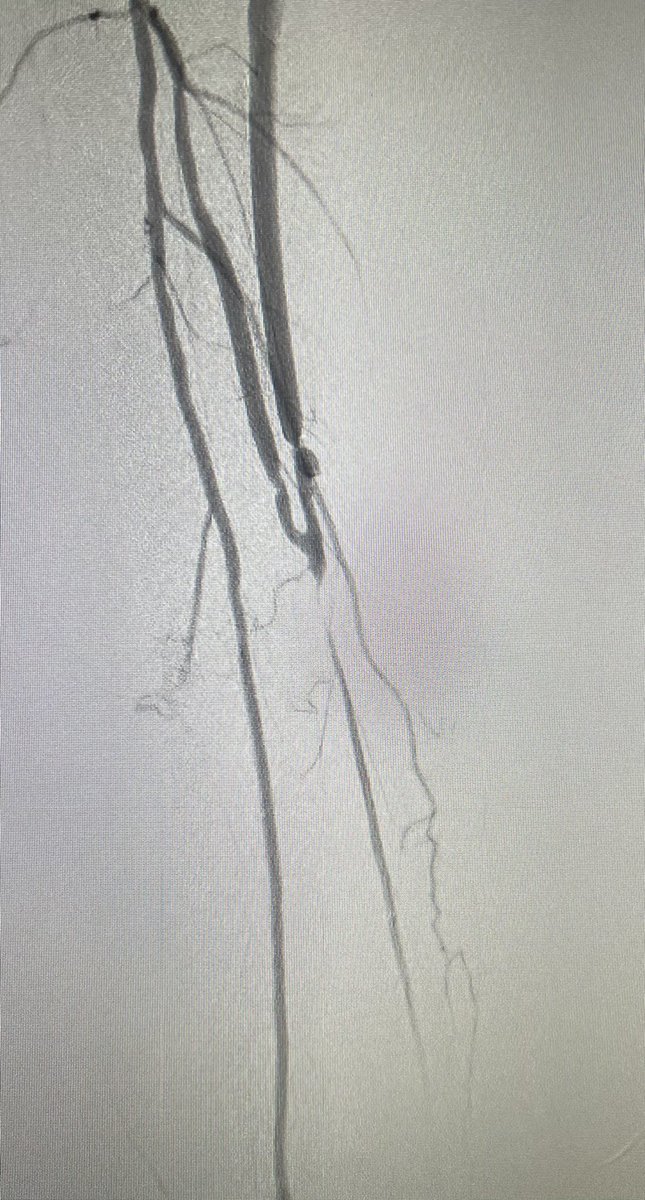

Vein bypass done 3 months for CLI. Wound healed but increasing pain in foot decrease in TBI and now this agram. What next?

@farkomd I like serranator balloons +/- dcb for these. POBAs seem to recoil too much. This is anecdotal though.